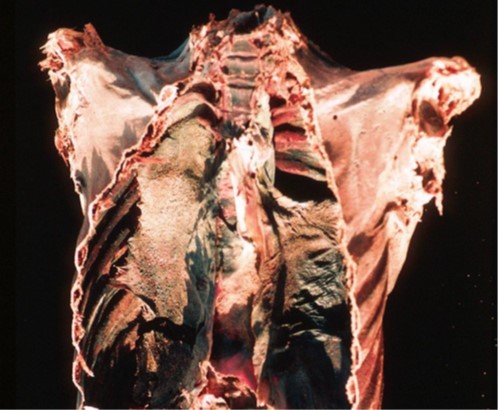

Tale procedimento non ha sicuramente favorito la conservazione dei polmoni stessi, ridotti dopo millenni ad una poltiglia densa difficilmente studiabile. Al di là delle evidenze di tubercolosi emerse dagli scheletri pervenutici (vedi https://laciviltaegizia.org/2023/01/21/virus-e-batteri/) anche il buon Ruffer, che abbiamo conosciuto come uno dei massimi esperti nello studio delle mummie all’inizio del XX secolo, trovò infatti una marea di difficoltà a fornire informazioni affidabili. Credette di aver ritrovato tracce di polmonite, ma tale interpretazione è ancora molto discussa.

In anni più recenti è stato invece possibile identificare con relativa certezza i segni di silicosi dovuta alla sabbia ed alla polvere di roccia, frequente negli scalpellini ancora oggi, e di antracosi dovuta all’inalazione del fumo di carbone – probabilmente frequente nei lavoratori delle necropoli o comunque dovuta ai fuochi mantenuti accesi nei luoghi chiusi – oltre a tracce molecolari di diversi virus respiratori. In epoca Covid qualche studioso aveva proposto anche di studiare i coronavirus rintracciati nelle mummie egizie per studiarne l’evoluzione.